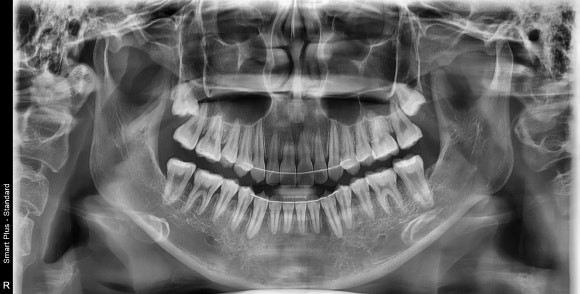

전체적인 환자의 모습은 위 아래 치아가 삐뚤어져 있었으며, 치아를 다물었을 때 위 아래 앞니가 닿지 않는 개방교합을 보이고 있었습니다. 참고로 원래 위 아래 치아끼리 다물었을 때 위 앞니가 아래 앞니보다 1~3mm 전방에 위치하면서 동시에 1~3mm 정도 수직적으로 덮는 것이 정상범주입니다.

삐뚤어진 치열을 가지런하게 하기 위해 공간 평가가 필요했고, 환자분의 얼굴 모습, 위턱과 아래턱의 관계, 교합 등을 종합적으로 분석하여 공간을 평가하였습니다. 그 결과, 발치 없이 만들 수 있는 공간량과 현재 공간 부족량이 비슷하다는 결과가 나와 발치를 하지 않고 교정치료를 진행하였습니다.

분석 결과, 치아가 뻐드러지지 않으며 현재 모습을 최대한 유지하면서 가지런히 만들고, 개방교합 교정도 하기로 했습니다. 그러기 위해 교정용 스크류도 식립하면서 치아 옆면 다듬기도 병행해 치료하기로 계획했습니다.